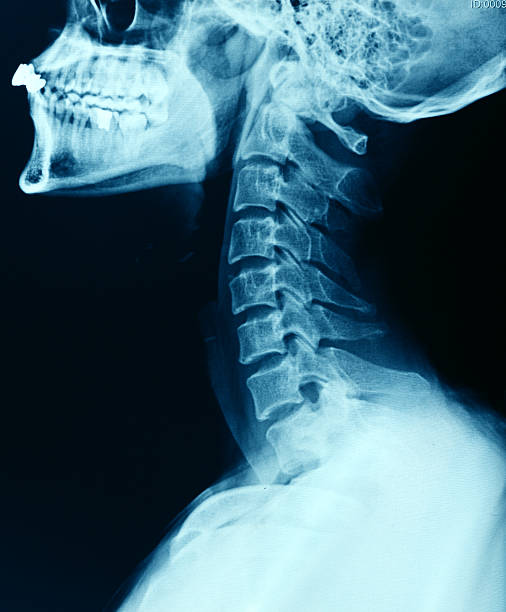

목 디스크는 일반적으로 노화로 인하여 수핵의 수분함량 감소로 탄력성이 떨어지거나, 나쁜 자세 습관과 같은 일상적인 움직임이나 외부의 자극으로 척추에 부담이 가해져 디스크가 손상되거나 이상이 생겨 통증을 일으키는 것을 목디스크라 합니다. 스마트폰 및 컴퓨터 사용량이 늘어나며 더욱 증가하고 있는 현대인의 대표적인 질병 목디스크. 과거에는 선천적인 요인 및 노화로 인하여 발생하는 증상이었지만 현재는 앞서 말씀드린 바와 같이 스마트폰, 컴퓨터 사용량 증가 및 잘못된 자세 등으로 인하여 아주 흔해진 질병입니다. 목디스크는 단순 목 근육통이 아닌 두통 및 팔 저림 증상까지 생기게 되는데요. 두통에서 그치지 않고 팔 저림 증상을 느끼게 된다면 그 즉시 정형외과에 방문하여 전문가의 정확한 진단을 받아보시는 것이 좋습니다. 인간의 척추는 경추 7개, 등뼈 12개, 허리뼈 5개, 천추, 미추로 `S` 자형 굴곡을 이루고 있습니다. 이런 굴곡 상태는 몸의 균형과 용수철 같은 탄력성으로 충격 완화 역할을 해줍니다. 척추뼈는 무거운 체중을 지탱해 주고 움직일 때 축의 역할을 해주는데요. 우리의 척추가 나이가 들고, 자세가 바르지 않다면 척추들을 연결하는 디스크가 닳고 수분이 빠져 쪼그라들어 키가 줄거나, 등이 휘어지고, 통증이 생기게 됩니다. 수십 개의 뼈로 연결된 척추의 뼈와 뼈 사이에 스프링처럼 몸의 충격을 흡수시켜 주고 완충 역할을 하는 것 일명 디스크라 불리는 추간판인데요. 목 디스크는 목 부위의 척추 간판(디스크)에 문제가 발생하여 발생하는 상황을 가리킵니다. 각 척추 간판은 외부에 경화된 외관과 내부에는 80%의 수 번성분의 젤리처럼 생긴 수핵과 이것을 보호하는 섬유 테들이 주위를 둥글게 감싸고 있습니다. 이러한 디스크는 척추 간의 충격을 완화하고 유연성을 제공하여 우리 몸이 움직이고 흡수하는 데 도움을 줍니다.

- 잘못된 생활 습관 - 사고로 인한 직접적인 외부 자극 - 지나치게 높은 베개를 사용할 때 - 컴퓨터나 핸드폰 사용 시 거북이처럼 목을 쭉 내빼고 사용하는 습관 - 컴퓨터 사용 시 눈높이가 아닌 너무 낮은 곳에서 사용하는 경우 - 과도한 체중, 디스크에 무리가 가는 무거운 물건 옮기기 - 자연적인 노화 이처럼 디스크는 우리 몸의 일상적인 활동과 부담으로 인해 손상을 입을 수 있습니다. 이에 따라 디스크가 터지거나 미세한 균열이 생길 수 있습니다. 이 때문에 디스크의 내용물이 디스크 자체를 벗어나거나 인접한 신경을 압박하여 통증을 유발할 수 있습니다. 목 디스크의 증상 및 진단 목디스크의 증상으로는 감각에 의한 통증과 마비 증상이 있습니다. - 목 통증: 목 부분의 지속적인 통증이나 긴장된 느낌이 있을 수 있습니다. - 팔, 어깨, 손가락의 통증: 목 디스크의 압박으로 인해 팔, 어깨, 손 등으로 전기가 오듯 더 심한 저린 느낌과 둔한 느낌을 받을 수 있습니다. - 근육 약화 또는 마비: 디스크 압박으로 인해 신경이나 척수에 압박이 걸리면 근육 약화나 마비가 발생하여 물건을 쥐는 힘이 떨어져 물건을 놓칠 수도 있습니다. - 두통: 목 디스크가 인접한 신경에 압박을 가하면 두통이 발생할 수 있습니다. 목디스크의 진단 단순히 목에 담이 왔다거나 근육통의 저림 증상인데 내가 목디스크인가? 라고 생각이 드시는 분들이 계실 수도 있는데요. 목디스크나 근육통의 증상은 비슷하지만 때는 해당 부위에 고통이 발생하나, 목 디스크의 경우는 해당 부위에 있는 신경이 자극되어 목을 움직일 때 통증이나 저림 감이 팔로 내려오게 됩니다. 해당 증상으로 병원에 내원하게 된다면 엑스레이 같은 단순 방사선 검사를 통해 목등뼈 부위의 전반적인 구조를 보게 됩니다. 만일, 상태가 심각한 상태라면 MRI, CT 등의 심층적인 촬영을 통해 디스크의 상태, 신경 압박 정도, 내부 구조를 자세히 볼 수 있습니다.